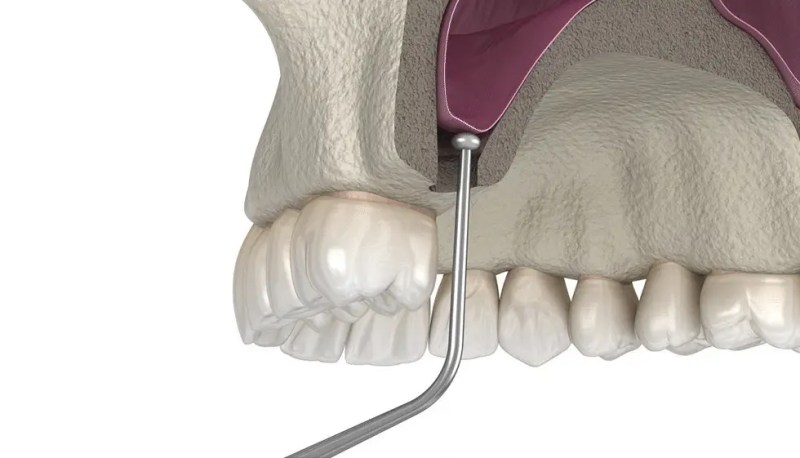

La elevación del seno maxilar es un procedimiento quirúrgico que agrega hueso a la mandíbula superior en el área de las muelas y premolares. Se realiza cuando no hay suficiente hueso en el área de la mandíbula para soportar un implante dental y el paciente ha sufrido pérdida ósea debido a la pérdida de dientes, enfermedad periodontal, falta de dientes congénita y traumatismo en la boca.

Los senos paranasales se encuentran a ambos lados de la nariz y encima de la boca. Cuando se pierden dientes, el hueso de esa zona comienza a deteriorarse o a encogerse. Esto suele provocar que se forme una bolsa debajo de la raíz del diente, lo que puede llevar a la pérdida del mismo. Dr. G En Dental Studio, realizamos un levantamiento de seno maxilar para reconstruir el hueso en esta zona y prevenir la pérdida ósea y la consiguiente infección de la raíz dental. La pérdida ósea en esta área generalmente se puede corregir con un implante dental, pero antes de colocar los implantes, es necesario elevar el piso del seno maxilar para que los implantes dentales tengan espacio suficiente.

Un procedimiento de elevación de seno o aumento de seno implica injertar hueso de la cadera del paciente en la mandíbula superior. El injerto óseo se inserta entre la mandíbula superior y los senos maxilares, las cavidades huecas a ambos lados de la nariz. Una vez que el injerto esté colocado, se fusionará con el hueso existente para crear una estructura estable y lo suficientemente firme como para soportar los implantes dentales.

La elevación del seno permite la colocación exitosa de implantes dentales en el maxilar posterior, donde la altura del hueso es insuficiente debido a la proximidad del seno maxilar. Al aumentar la altura del hueso, una elevación de seno crea una base estable para la colocación de implantes dentales, mejorando su longevidad y tasa de éxito.